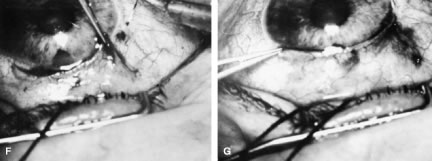

incision, or it can be coapted with the wet-field cautery.   Fig. 11. Fornix-based flap procedure. A. With a scissors or knife, the conjunctiva is incised as close to the limbus

as possible. B. The incision is widened. The surgeon uses forceps to stretch the tissue. The

scissors cut inferiorly so that no remnant of conjunctiva is left

on the globe. C. Tissue is separated from the globe by inserting the scissors with the

tips closed and then spreading them bluntly. D. Blunt dissection is continued until the sclera is cleaned adequately. Bleeding

from the cut conjunctival vessels is almost inevitable and usually

exceeds the bleeding that occurs when a limbus-based flap is raised. E. A radial cut at the edge of the peritomy will improve visualization of

the sclera and permit a neat closure of the conjunctiva. F. The cut edge of a fornix-based flap is pulled inferiorly and secured with

a 10-0 nylon purse-string suture. G. With large incisions, it usually is necessary to suture both edges to

ensure tight closure. (Spaeth GL. Glaucoma surgery. In Spaeth GL (ed). Ophthalmic Surgery: Principles

and Practice. Philadelphia: WB Saunders, 1990.) Fig. 11. Fornix-based flap procedure. A. With a scissors or knife, the conjunctiva is incised as close to the limbus

as possible. B. The incision is widened. The surgeon uses forceps to stretch the tissue. The

scissors cut inferiorly so that no remnant of conjunctiva is left

on the globe. C. Tissue is separated from the globe by inserting the scissors with the

tips closed and then spreading them bluntly. D. Blunt dissection is continued until the sclera is cleaned adequately. Bleeding

from the cut conjunctival vessels is almost inevitable and usually

exceeds the bleeding that occurs when a limbus-based flap is raised. E. A radial cut at the edge of the peritomy will improve visualization of

the sclera and permit a neat closure of the conjunctiva. F. The cut edge of a fornix-based flap is pulled inferiorly and secured with

a 10-0 nylon purse-string suture. G. With large incisions, it usually is necessary to suture both edges to

ensure tight closure. (Spaeth GL. Glaucoma surgery. In Spaeth GL (ed). Ophthalmic Surgery: Principles

and Practice. Philadelphia: WB Saunders, 1990.)

|